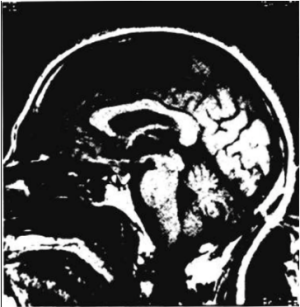

- Neuroimaging studies such as head and orbital CT and/or MRI with and without contrast [1]

Radiographic features vary depending on the etiology but generally, an intracranial mass causing optic nerve compression and resulting in features of optic atrophy can be seen.[3]